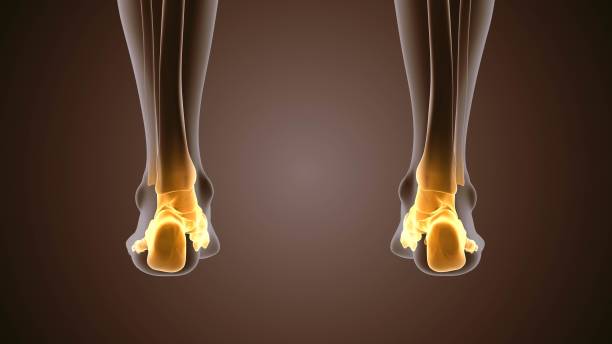

발뒤꿈치가 아픈 이유 세 번째는 점액낭염입니다. 점액낭은 아킬레스건의 움직임을 부드럽게 해주는데 이 역시 반복된 충격을 가하기 때문에 발뒤꿈치에 통증이 생길 수 있습니다. 다만 아킬레스건과 다르게 평소에도 통증이 지속되기 때문에 지속적인 관리를 해야합니다.

발뒤꿈치가 아픈 이유 네 번째는 지방 패드 위축 증후군입니다. 발뒤꿈치와 발 앞부분에는 피부와 뼈 사이에 탄력 있는 지방 조직이 있어 페달링의 충격을 흡수합니다. 여기에 너무 많은 압력을 가하거나 나이가 들어감에 따라 지방조직이 퇴화되어 수축하면 완충액이 제대로 기능하지 못해 염증과 통증을 유발한하는데 지방 패드 위축 증후군은 처음에 발을 디딜 때는 괜찮으나 한참을 걷다보면 통증을 느낄 수 있으며 이로 인해 발바닥의 피부가 두꺼워져 지방 패드의 수축을 보상하기 위해 굳은살이 형성됩니다.